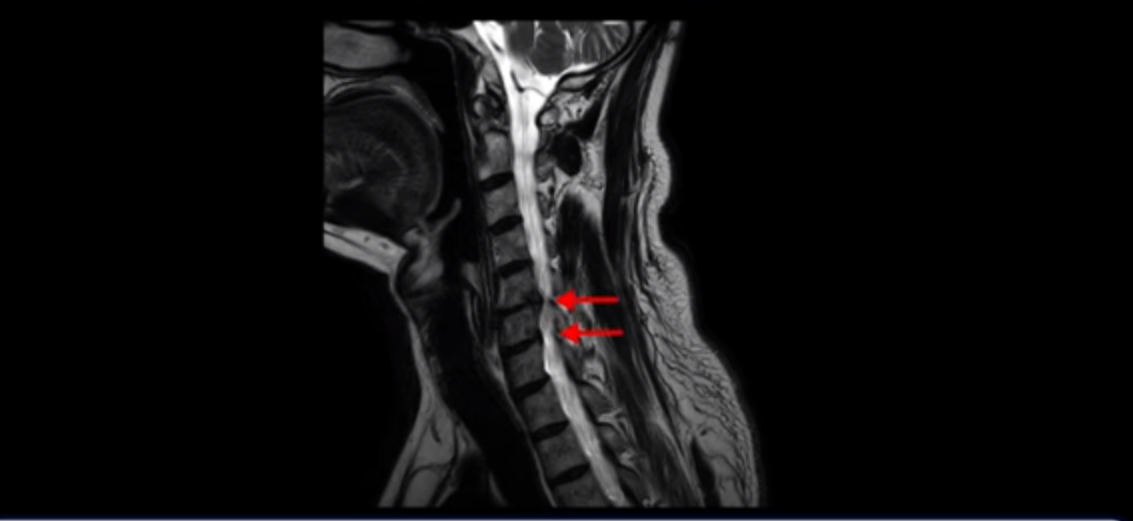

우선 이분 증상은 좌측 어깨와 팔 통증입니다. 이분 MRI를 보면 5번 6번과 6번 7번이 안 좋아 보입니다.

왼쪽으로 신경이 빠져나가는 추간공을 보면 보시다시피 5번 6번과 6번 7번 신경 구멍이 아래나 위에 비해 막혀있는 게 보입니다.

이분 왼쪽 어깨와 팔 통증이 갑자기 생긴 이유는 5번 6번 디스크 또는 6번 7번 디스크가 갑자기 밀려 나온 것이 원인일 것으로 보이는데, 그럼 이 디스크들이 밀려 나와서 신경을 자극하거나 누르는데 어떻게 이게 수술 없이도 좋아질 수 있는 걸까요?